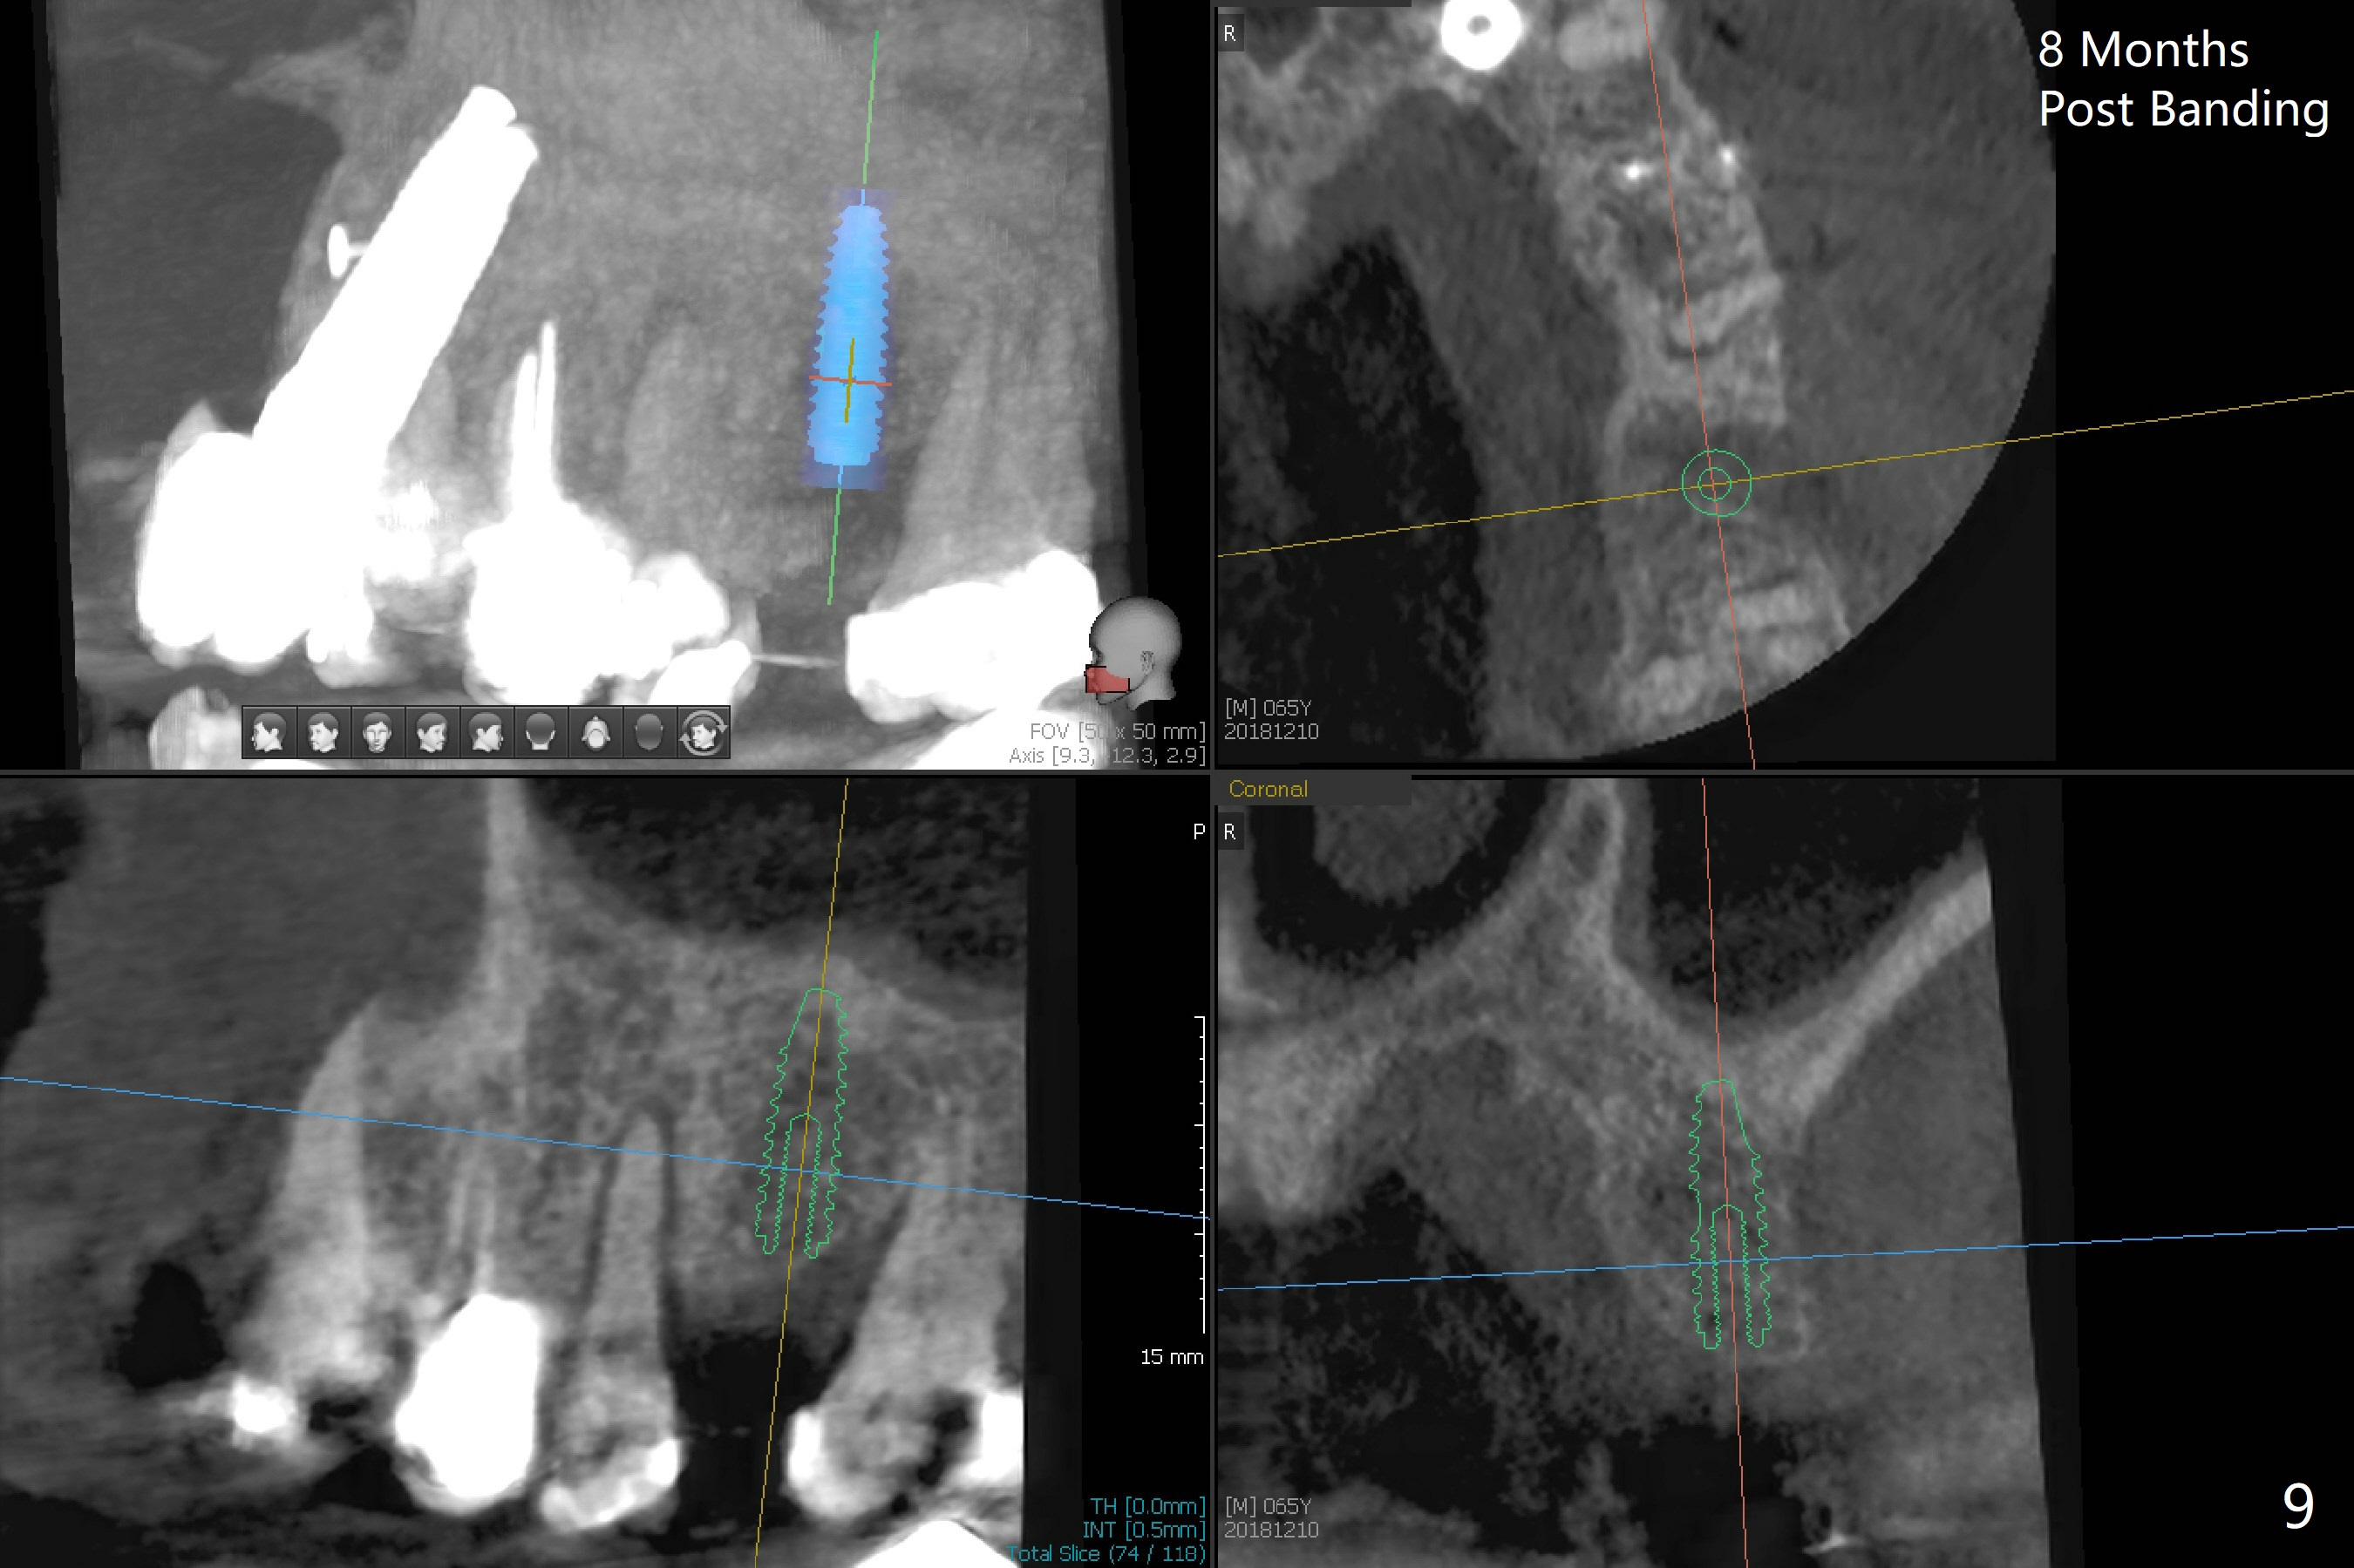

Ultradent Prime and Bond is used bracketing. The bonding system appears to be able to attach the brackets to porcelain crowns at #10 and 12 (Fig.3 (14 niti wire)). The 14 niti wire is not fully engaged (Fig.4). An open coil spring is used when the wire changes to 18 ss (Fig.5,6). Composite is placed to have clearance for UL7 to be distalized (Fig.5 *). To have the best anchor involving the implant at UL2, ligature wire is used between UL2-5 (Fig.6). In fact the anterior teeth are not good anchor. The bracket detaches from UL2 (implant) and UL5 keeps rotated, while UL7 is not distalized when open coil spring is placed between UL5-7. Nearly 6 months post banding, a 1.6x8 mm anchor pin is placed (Fig.7,8). Next visit the pin is loose and replaced with a ball type 1-piece implant (2x10(2) mm). Although the latter remains apparently stable, UL7 appears to remain in place. It seems necessary to place a restorative implant at UL6 as a future anchor (Fig.9: 3.5x11.5 mm).